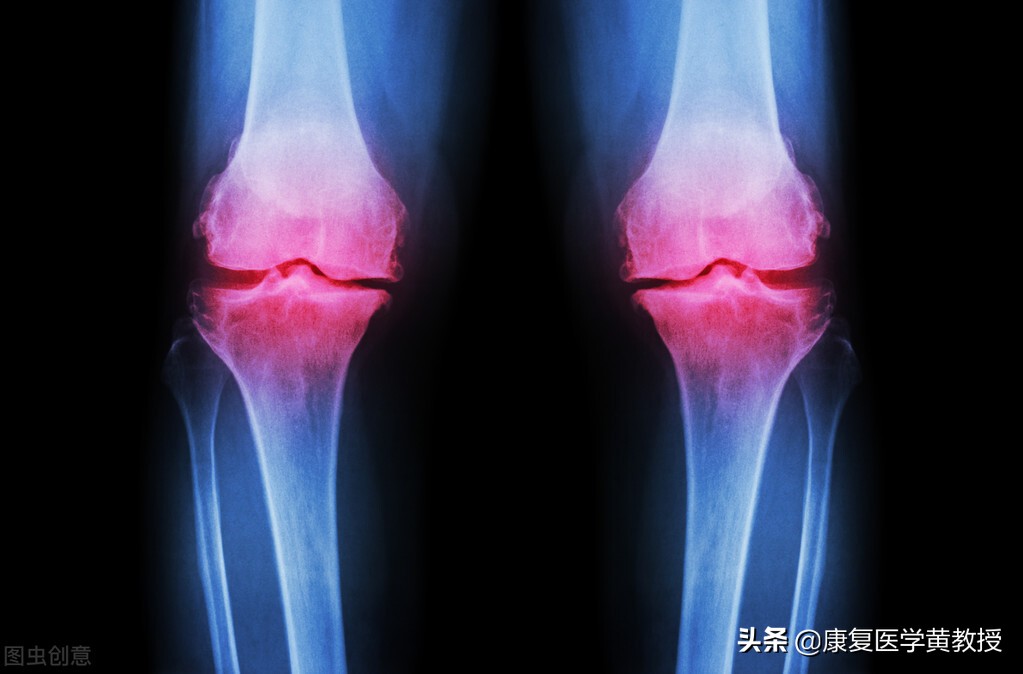

只是,骨刺增生有好的一面,必然也可能有弊端,比如膝关节开始骨质增生,同时代表的是半月板开始丧失缓冲减震的能力,只好利用骨头来分担压力,同时因为骨刺占据了原本不应该存在的空间,使得关节腔变小变窄,而影响膝关节的关节动力学表现,比如肌力下降,关节活动度下降,无法蹲起,生活品质下降,甚至加大腰椎与髋关节的压力,引发一系列的不正确的代偿模式,各位发现了吗?膝关节疼痛的患者,75%以上都伴随着腰痛或腰椎间盘膨出现象,这都是人体的连锁反应,无可避免.